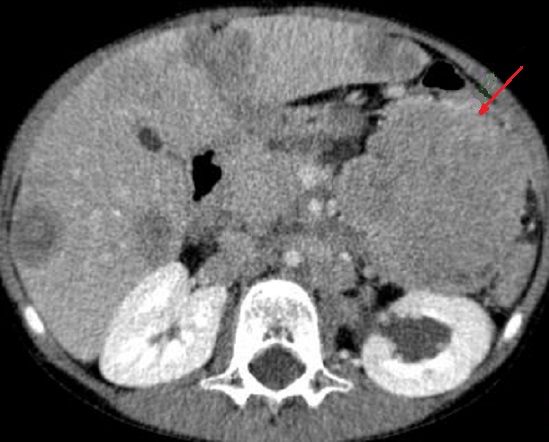

En association de lymphome de

la

queue du pancreas on peut retruuver image des

adenopathies aspect hypodense ovalaire situe sous diapragmatique (

fleche rouge ) . Image radiologique TDM en coupe

axilaire |

|

Des adenopahthies de tumeur lymphoide

peut situe sous ou perihilaire renale ( fleche

rouge ) . Une caracteristique des lymphomes

pancreatiques est l'absence de envahissement

vasculaire et l'absence de metastase hepatique |